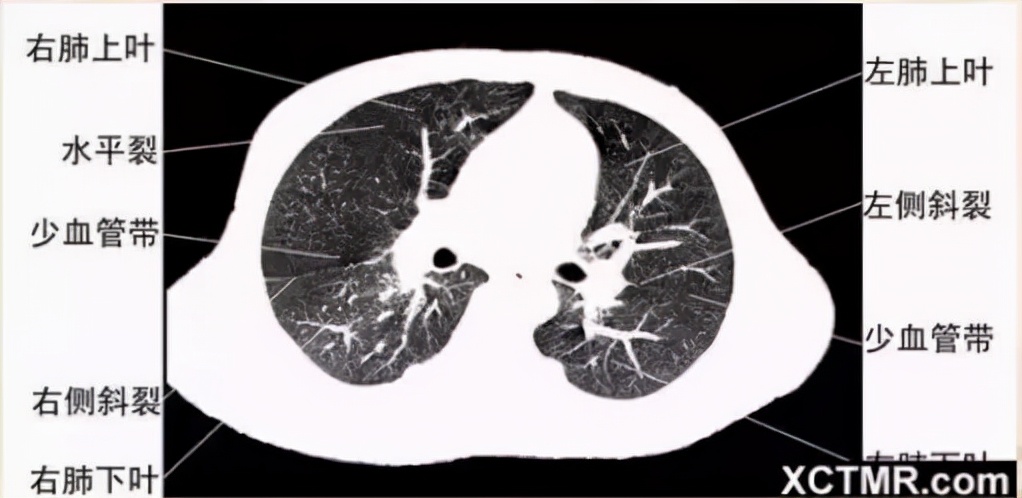

左主支气管层面